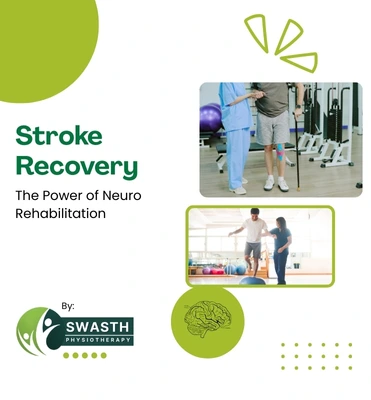

"After my father’s stroke, we were worried about his recovery and mobility. The home care physiotherapy services from Swasth Physiotherapy made a huge difference. Slowly he started sitting, standing and walking with support. Their neuro & stroke rehabilitation in Visakhapatnam is very systematic, patient-friendly and effective

Swasth Physiotherapy offers Home Care Services for elderly patients, post-surgery cases, stroke patients and those who find it difficult to travel to the clinic.